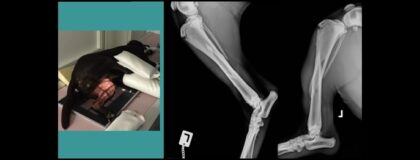

Online-Seminar: OP-Assistenz für TFA 7 - Röntgenlagerung von orthopädischen Patienten

In diesem vetinar lernen Sie die Grundlagen der Röntgenlagerung von orthopädischen Patienten kennen. Nach einer allgemeinen Einführung werden die speziellen Lagerungen von den einzelnen Gliedmaßenanteilen mit Hilfe von Beispielen demonstriert. Wertvolle Tipps und Tricks dienen dazu, den Zugang für eine einfache Lagerung zu finden. Auch werden tiefere Einblicke in die Röntgendiagnostik von verschiedenen orthopädischen Fällen gegeben.